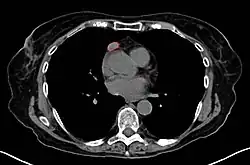

When a thymoma is suspected, a CT/CAT scan is generally performed to estimate the size and extent of the tumor, and the lesion is sampled with a CT-guided needle biopsy. Increased vascular enhancement on CT scans can be indicative of malignancy, as can be pleural deposits.[2] Limited biopsies are associated with a very small risk of pneumomediastinum or mediastinitis and an even-lower risk of damaging the heart or large blood vessels. Sometimes thymoma metastasize for instance to the abdomen.[6]